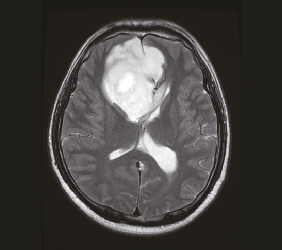

3. 영상 검사

- MRI(자기공명영상) : 교모세포종을 진단하는 데 가장 중요한 검사입니다. 조영제를 사용한 MRI는 종양의 위치, 크기, 침습 정도를 상세히 보여줍니다.

- CT(컴퓨터단층촬영) : MRI가 불가능한 경우 또는 뇌출혈 등 급성 상태를 평가할 때 사용됩니다.